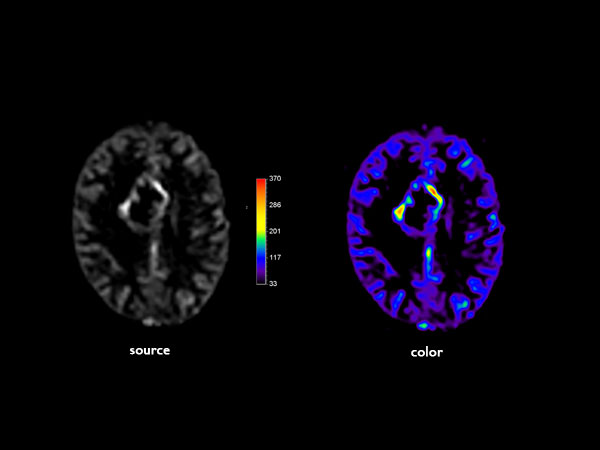

Advanced Neuro imaging - pCASL

Clinique Saint Joseph Imagerie Medicale, Liege, Belgium